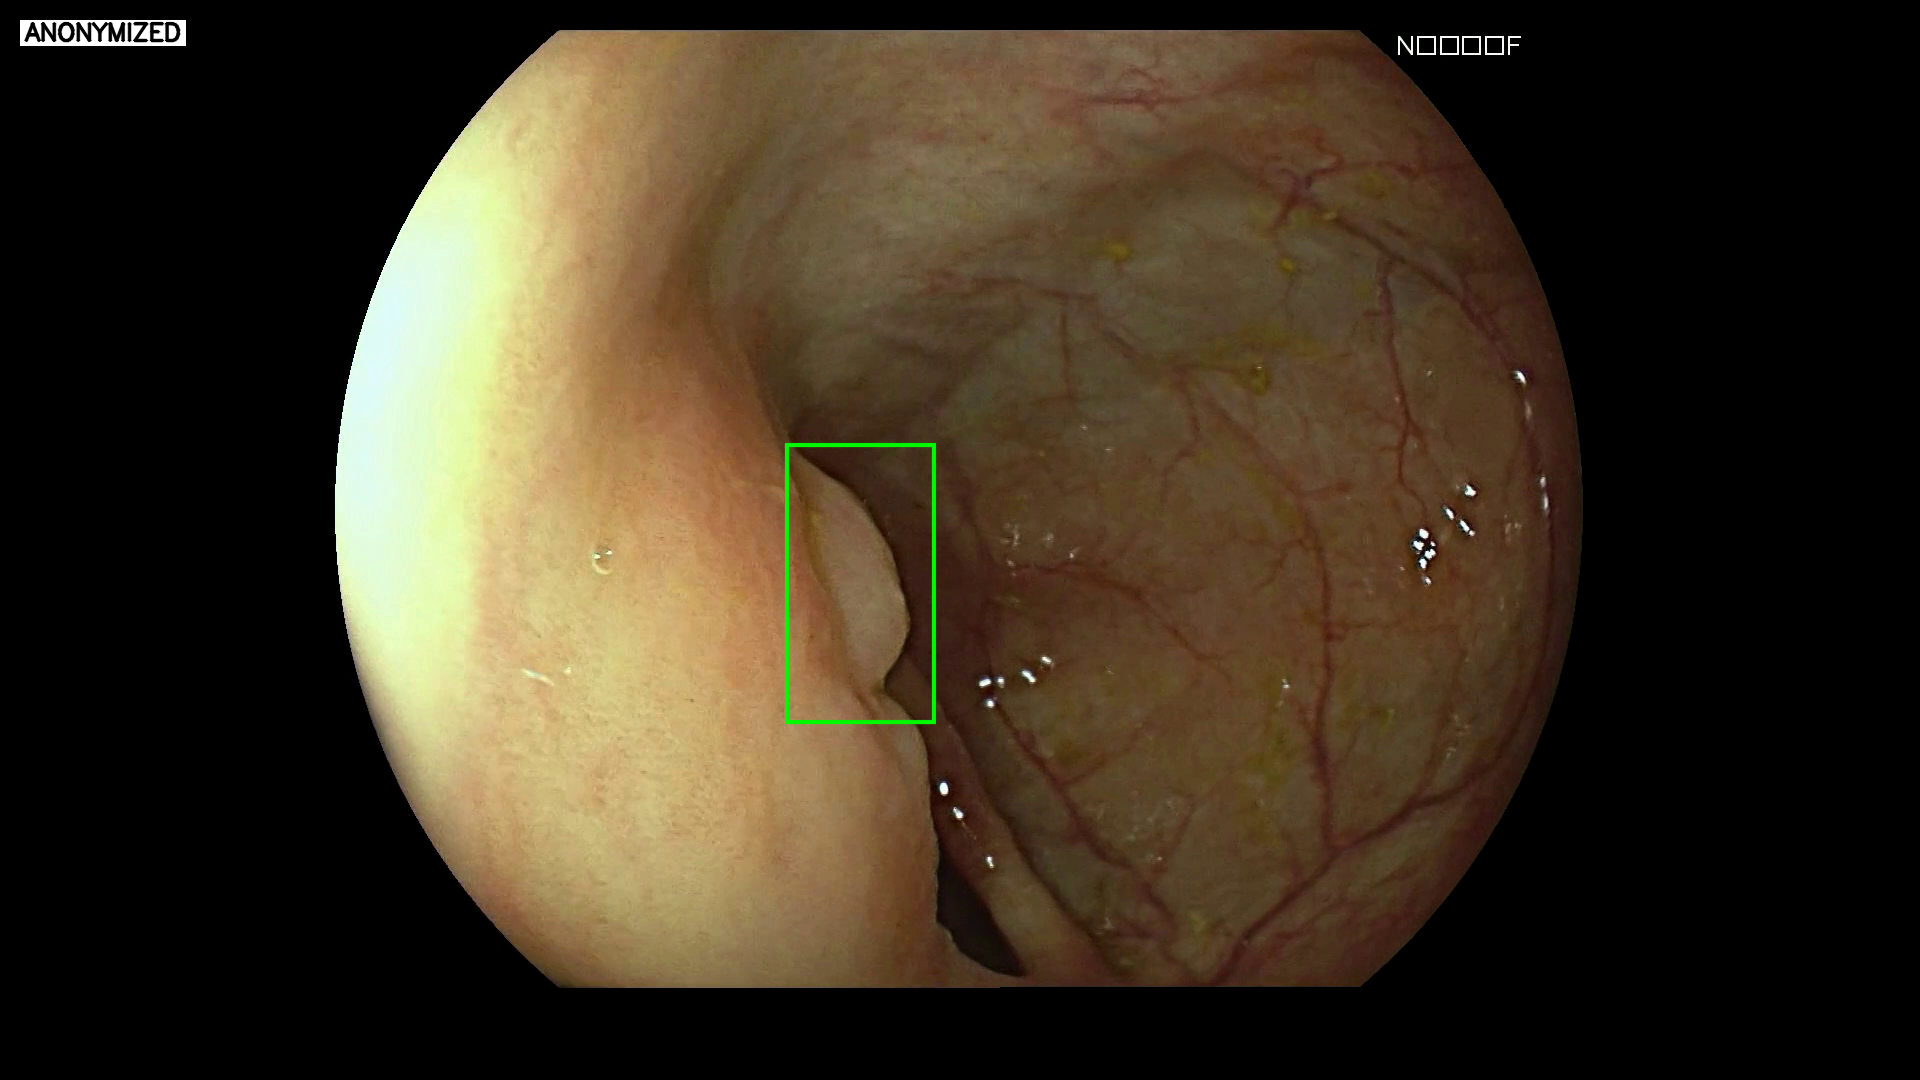

Colorectal polyp detection

Recurrent neural networks